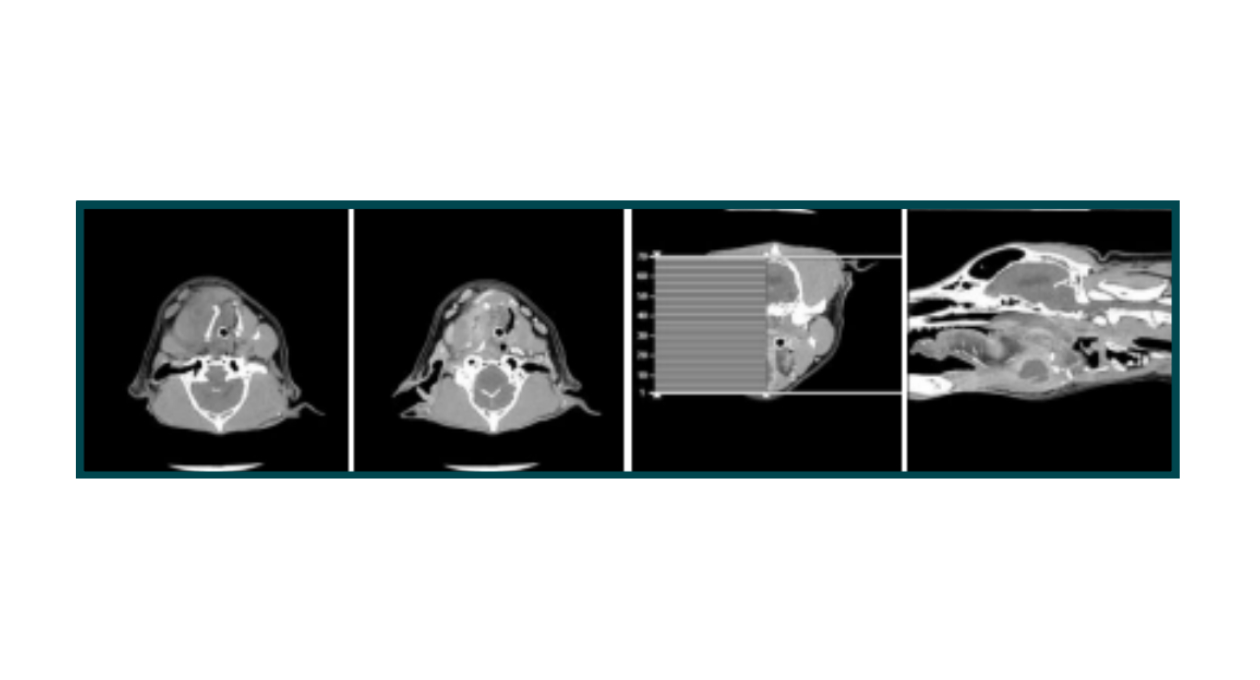

A CT scan was performed emergently, revealing a large left peripharyngeal abscess, which was causing significant compression of the oropharynx and nasopharynx, leading to Cato's breathing difficulties. The scan showed no foreign material, osseous involvement, or soft tissue gas, and it was concluded that the findings were most consistent with an abscess rather than neoplastic tissue.